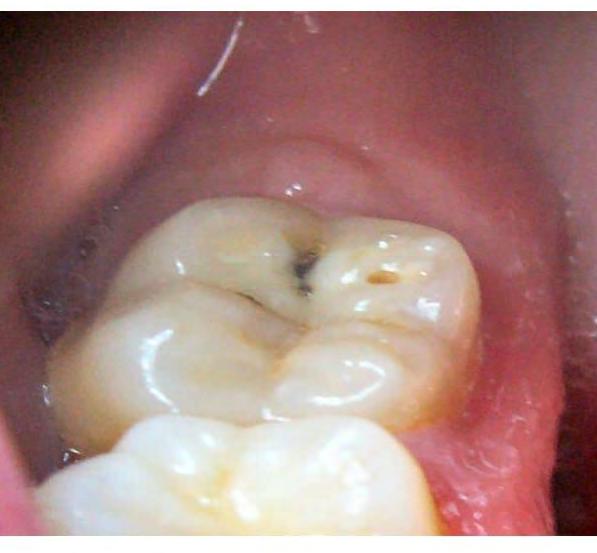

Cáries - Lesão que se inicia na parte externa do dente que, pelo acúmulo de placa bacteriana, sendo uma película viscosa e incolor, formada de açúcares, restos de alimentos e bactérias, conseguem destruir o Esmalte do dente, uma estrutura dura e mineralizada. Após destruir o esmalte dentário, a cárie começa a se infiltrar para a parte interna do dente. A cárie se forma através da reação da placa bacteriana com açúcares dos alimentos que consumimos, produzindo ácidos que atacam o esmalte dentário e deixando os dentes vulneráveis, permitindo que a cárie se desenvolva ainda mais. Caso a cárie não seja tratada e detectada com antecedência, ela poderá evoluir e causar diversos problemas mais graves como: infecções , contaminações, morte da polpa do dente e até a extração dentária.